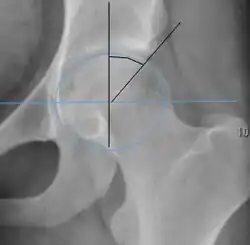

Measurements of impingement on X-ray.[notes 1][20]

Measurement Image Target Normal value

Center-edge angle of Wiberg

The superior-lateral coverage of the femoral head.

• >20° (<55 years old)[notes 2]

• <24° (>55 years old)[notes 2]

• >40° indicates overcoverage

Crossing ratio Percentage of acetabular walls crossing. Normal acetabulum is oriented in anteversion. Its value ranges from 15 to 20° in the equatorial plane of the acetabulum and decreases gradually towards the acetabular roof, where normal values range from 0 to 5°. Retroversion of the upper part of the acetabulum has been related with pincer type impingement. In radiography the presence of a "crossover sign" is produced when the posterior wall of the acetabulum crosses the anterior wall before reaching the acetabular roof. It is a sign of acetabular retroversion and it has been linked with overcoverage and pincer impingement. Nevertheless, this sign has been described in 6% of the normal population. Therefore, more important than its presence is the percentage of crossing. <20%

• Higher is significant crossing

Alpha angle

Measured in 45° Dunn view.

Degree of bulging of the femoral head-neck junction: In normal conditions there is a symmetric concave contour at the junction of the femoral head and neck. Loss of this concavity or bone bulging may lead to cam type impingement. The degree of this deformity can be measured by the alpha angle. Although it can be measured in the cross-lateral view, the 45° Dunn view is considered more sensitive and the frog leg view more specific in determining pathologic values.

• Normal: ≤68° in men, ≤50° in women

• Borderline: 69° to 82° in men, 51° to 56° in women

• Pathological: ≥83° in men and ≥57° in women

Femoral head-neck offset

Measured in cross-lateral view.

Offset of the femoral head with regard to most prominent aspect of the femora neck >10 mm

Offset percentage Femoral head-neck offset related to femoral head diameter >0.18

• less indicates high risk of cam type impingement

Tönnis angle Slope of the sourcil (the sclerotic weight-bearing portion of the acetabulum) 0 to 10°

• >10° is a risk factor for instability

• <0° is a risk factor for pincer impingement

Caput-sourcil angle[21] Superior to the Tönnis angle in cases without joint space narrowing or subluxation.[21] The medial point of the sourcil is at the same height as the most superior point of caput femoris. −6 to 12°[21]

• >12° is a risk factor for instability

• <-6° is a risk factor for pincer impingement